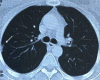

Primary psoas tuberculosis abscess with an iliac bone lytic lesion: a case report

Case presentation: In this report, we present a challenging diagnostic case of primary psoas tuberculosis in a 38-year-old middle eastern female from southern Syria. The diagnosis was based on the clinical orientation, the observation of pulmonary lesions on the computed tomography scan, and the necrotic signs in the vicinity of the infected area. Despite the misleading primary false-negative results, the final diagnosis was reached after sufficient repetition of tuberculosis-specific testing. The patient was treated with isoniazid-rifampin-pyrazinamide-ethambutol for 2 months, then isoniazid and rifampin for 7 months, with full recovery in follow-up.